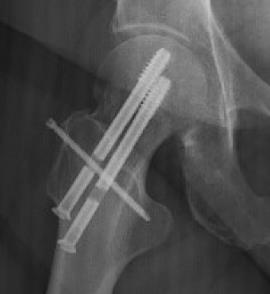

SimpliFix Hip System

• The SimpliFix Hip System is a percutaneous fixation construct for minimally displaced or non-displaced intracapsular femoral neck fractures, designed to mitigate complications seen with parallel screw constructs or dynamic hip screw alone. The system pairs two large-diameter cannulated screws with a targeted headless cross screw that keys through a slot in the superior screw to add rotational control. Using a dedicated targeting arm, the surgeon selects 0 mm (no dynamization) or 3 mm (controlled settling) of compression to help resist femoral neck shortening while maintaining native neck length and femoral offset.

• The cross-screw technique enhances rotational stability and helps prevent lateral head migration, supporting alignment and reducing the risk of additional shortening. Preserving femoral neck length correlates with improved pain and function in postoperative recovery, making controlled compression and rotational control clinically meaningful endpoints.

• SimpliFix trajectories place an inferior calcar screw for axial support and a central–superior screw oriented toward the anterior–superior head, preserving bone stock while providing a dedicated slot for the cross screw.

• These vectors resist varus collapse and shortening.

• Drive and seat the inferior SimpliFix cannulated screw (Ø 8.3 mm, 16 mm thread, blunt, self-tapping head).

• Assemble the SimpliFix T-handle and retaining bolt; secure the superior SimpliFix screw (ensure fins engage the mating slots).

• Insert the headless cross screw (Ø 3.7 mm) with a T8 driver; power to near seat, then hand-seat to cortex.

• Final verification: anteroposterior and lateral fluoroscopy to confirm reduction, implant positions, and cross-screw engagement with the superior screw slot.